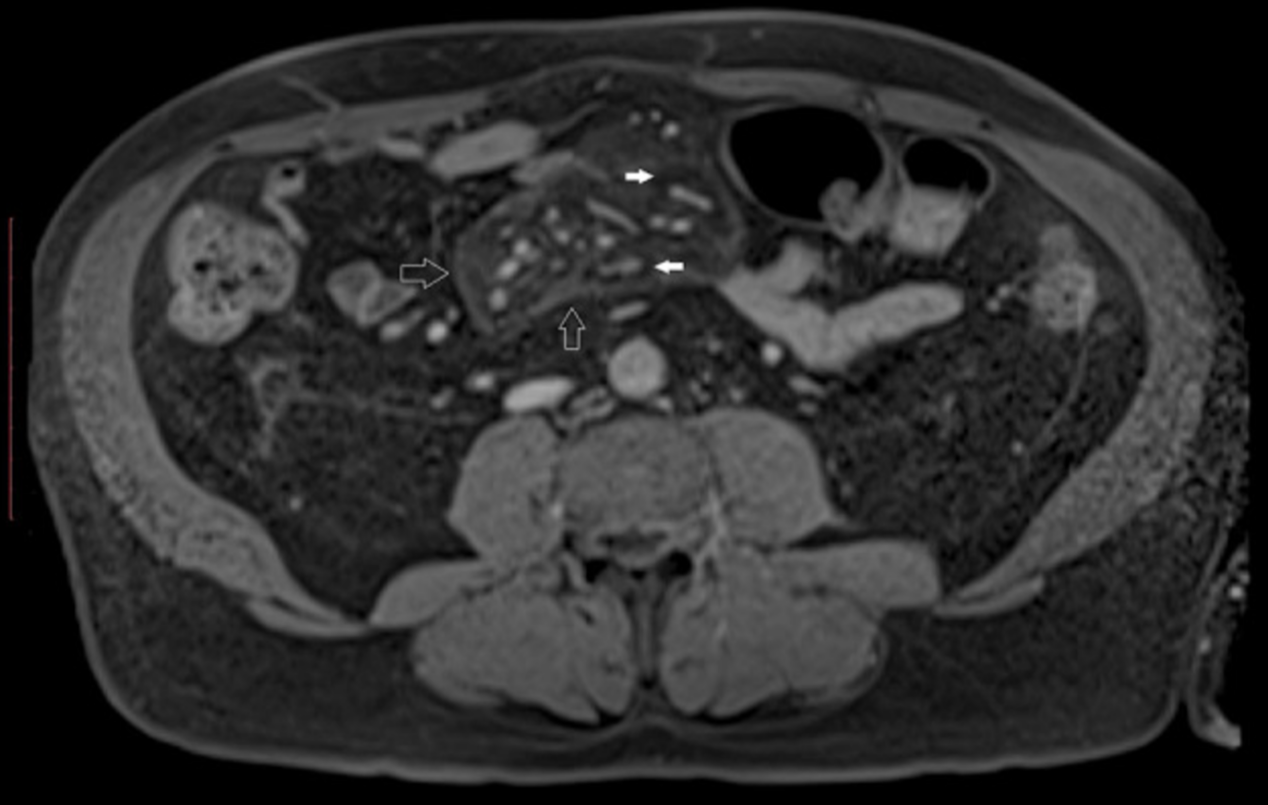

血液检查显示高糖化血红蛋白水平(12%,108mmol/mol)和白细胞增多(13.57%×103/μl) 其他炎症标志物(C反应蛋白、血沉)无增加。腹部超音波显示左肾有小肾囊肿(图1)。

图1

作为初始治疗,连续静脉注射胰岛素。在住院的第三天,我们用每日多次注射胰岛素代替静脉胰岛素输注。尽管静脉注射胰岛素,血糖控制仍然不理想。由于这一事实和持续的腹痛,计算机断层扫描(CT)进行。CT显示肠系膜脂肪组织有不典型的增强区。双肾均可见肾囊肿;但是被排除在腹痛的原因之外。结肠镜和胃镜检查没有发现任何异常。

腹部增强磁共振成像(MRI)证实了肠系膜异常。硬化性肠系膜炎根据CT和MRI诊断。由于患者出现持续性腹痛,每天给予强的松40mg。该治疗减少了腹痛,改善了血糖控制,这表明胰岛素需求量较低(胰岛素的总平均日剂量为32 IU SC)。